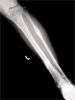

Post

Op

Treated with closed reduction, ligamentotaxis and ring fixator.Fibula brought to length by IM rod